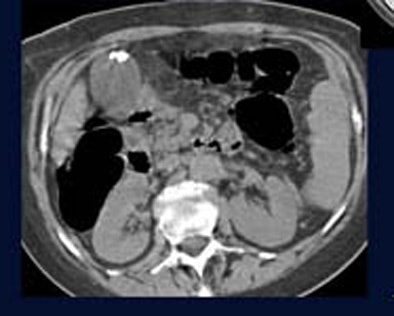

![]() |

| The prevalence of potentially clinically important findings was similar between mostly screening patients and mostly symptomatic patients. (Group A [n=185] included 84 asymptomatic screening patients, 43 presenting with abdominal pain, 30 with incomplete conventional colonoscopy, and 28 patients with known diverticulosis. Group B patients [n=76] underwent contrast-enhanced VC, and included 36 patients examined for tumor staging, 36 for follow-up VC, and 10 with positive FOBT exams.) |